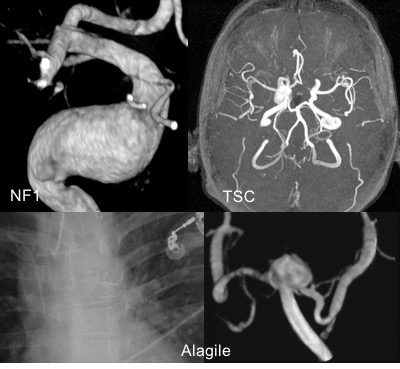

- maladies artérielles : ci-dessous sont représentés des exemples d’anévrysmes associés à la maladie de Recklinghausen, de Bourneville, d’Alagile